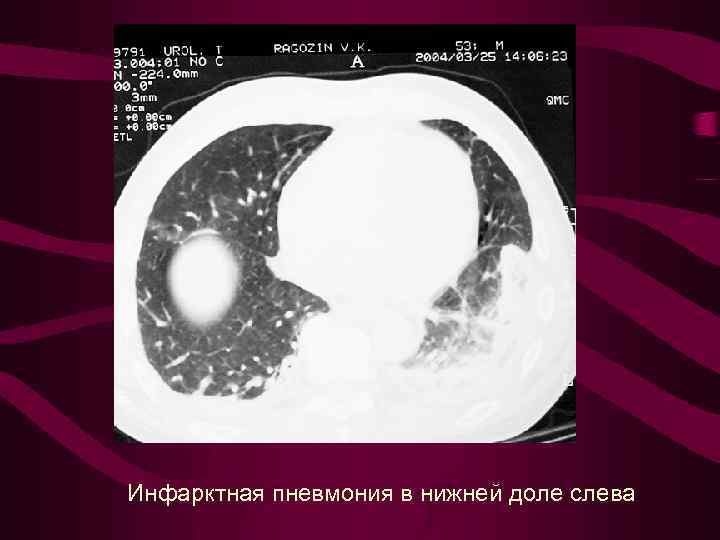

Инфарктная пневмония в нижней доле слева

Инфарктная пневмония в нижней доле слева